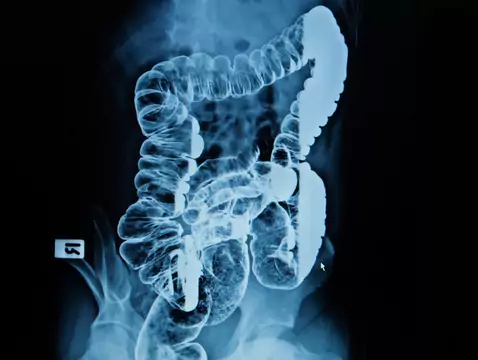

Angiodysplazja jelitowa zaliczana jest do naczyniowych wad rozwojowych obejmujących jelita. Wielu pacjentów zgłasza się do specjalisty- gastrologa z dziwnymi, nieprzewidywalnymi krwawieniami...